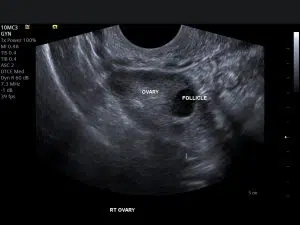

- Ovaries: The two small organs that produce eggs and hormones.

- Transvaginal ultrasound: A smaller probe is gently inserted into your vagina to get a closer look at your pelvic organs. This type of scan provides more detailed images of the uterus and ovaries.

- Infertility: Ultrasounds can help assess the health of your uterus and ovaries, and check for any conditions that may be affecting your fertility.

- Polycystic ovary syndrome (PCOS): PCOS is a hormonal disorder that can affect the ovaries.

- Ovarian cysts

- Polycystic ovary syndrome (PCOS)

Read MoreFollicle Tracking Scan

Follicle Tracking Scan London Follicle tracking ultrasound is a precise...